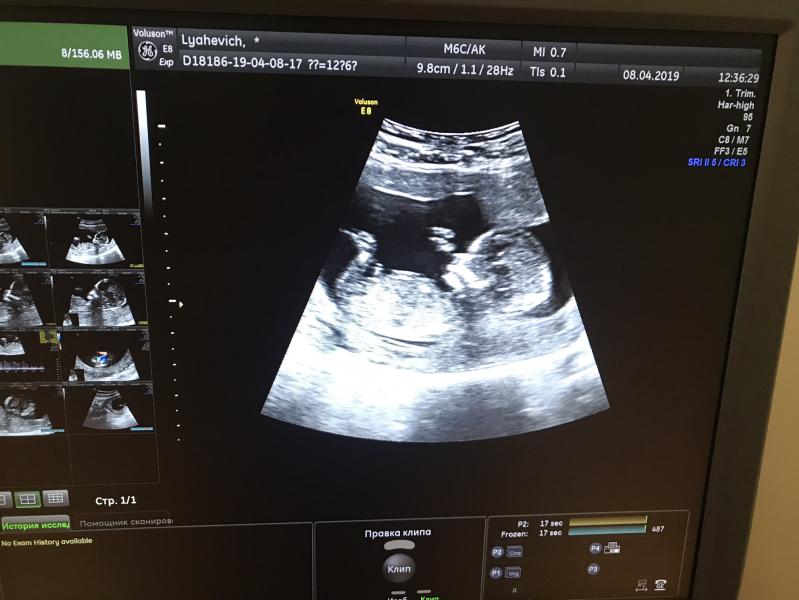

Боже какое это счастье 🥰😍 слышать «ваш ребёнок развивается согласно сроку» я разревелась прям в кабинете😭 с дочкой такого не было 🤪 вообщем, знакомьтесь это наш второй малыш 😇 или малышка 😇 по параметрам с первой дочкой все один в один 🥰 как же я счастлива 😋

Так хорошо на фото видно и носик и ручки😍😍😍